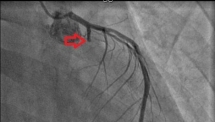

Sau một lần đi khám sức khỏe định kỳ tại Bệnh viện 108, người đàn ông hút thuốc lá lâu năm phát hiện bản thân bị hẹp khít mạn tính động mạch vành.

Mới đây, các bác sĩ Bệnh viện Nhân dân 115 (TP.HCM) vừa cấp cứu cho nam bệnh nhân bị nhồi máu cơ tim cấp khi chỉ mới 25 tuổi.